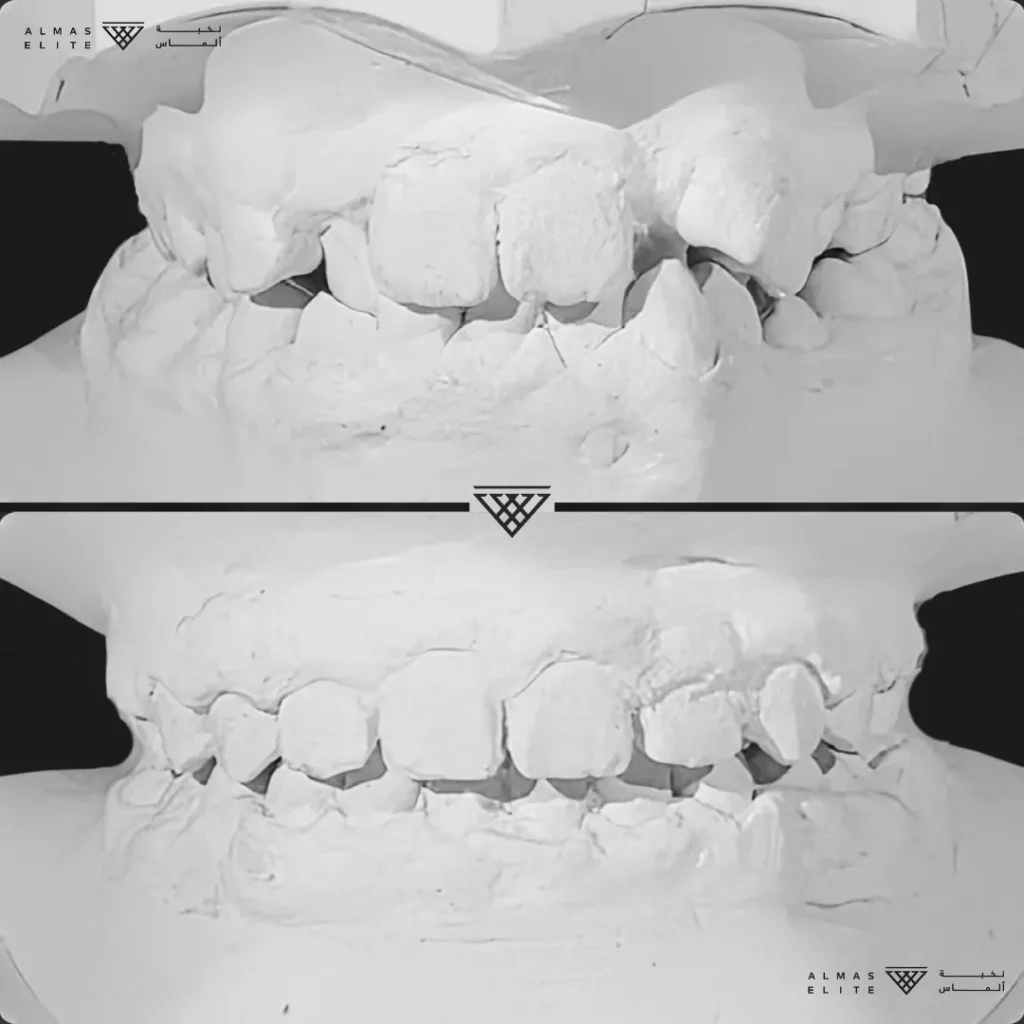

٢) التقييم والتشخيص الشامل

يشمل صور الأشعة والتحليل الرقمي للأسنان والفكين للوصول إلى تشخيص دقيق.

- تشخيص دقيق يشمل الأشعة والتحليل الرقمي للأسنان والفكين.